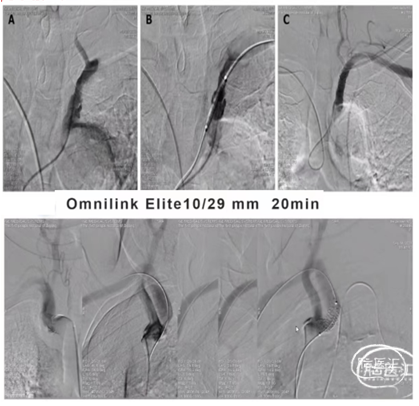

(二)高位椎动脉狭窄经绕同侧入路椎动脉狭窄支架置入

1、椎动脉狭窄,如果开口向外侧,行同侧桡动脉入路时角度顺行,可选择同侧桡动脉置入6F动脉鞘,0.035泥鳅导丝置于病灶侧锁骨下动脉起到或单弯同轴将6F导引导管到达狭窄椎动脉附近,微导丝导引球囊扩张支架(4-5mm)铆定狭窄部位后扩张释放支架。

1、双侧桡动脉置入6F动脉鞘。健侧进行造影定位和观察。

患侧将0.035in泥鳅导丝通过狭窄进行小球囊扩张(3-3.5mm)建立通路,撤出球囊。

沿泥鳅导丝(不用导引导管)将7-10mm球扩支架到位,通过对侧造影铆定后球囊扩张释放。

2、输送7-10mm球扩支架时不需要导引导管,直接沿泥鳅导丝输送,球扩支架不释放时小于2.5mm,能够顺利通过桡动脉。